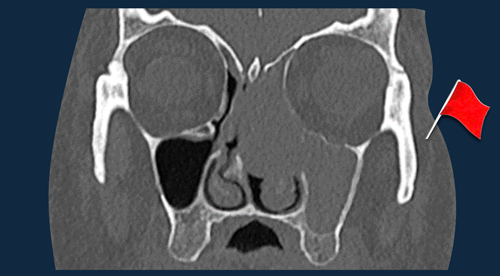

Head Neck tumors - When to think of malignancy

Head Neck tumor - any red flags?